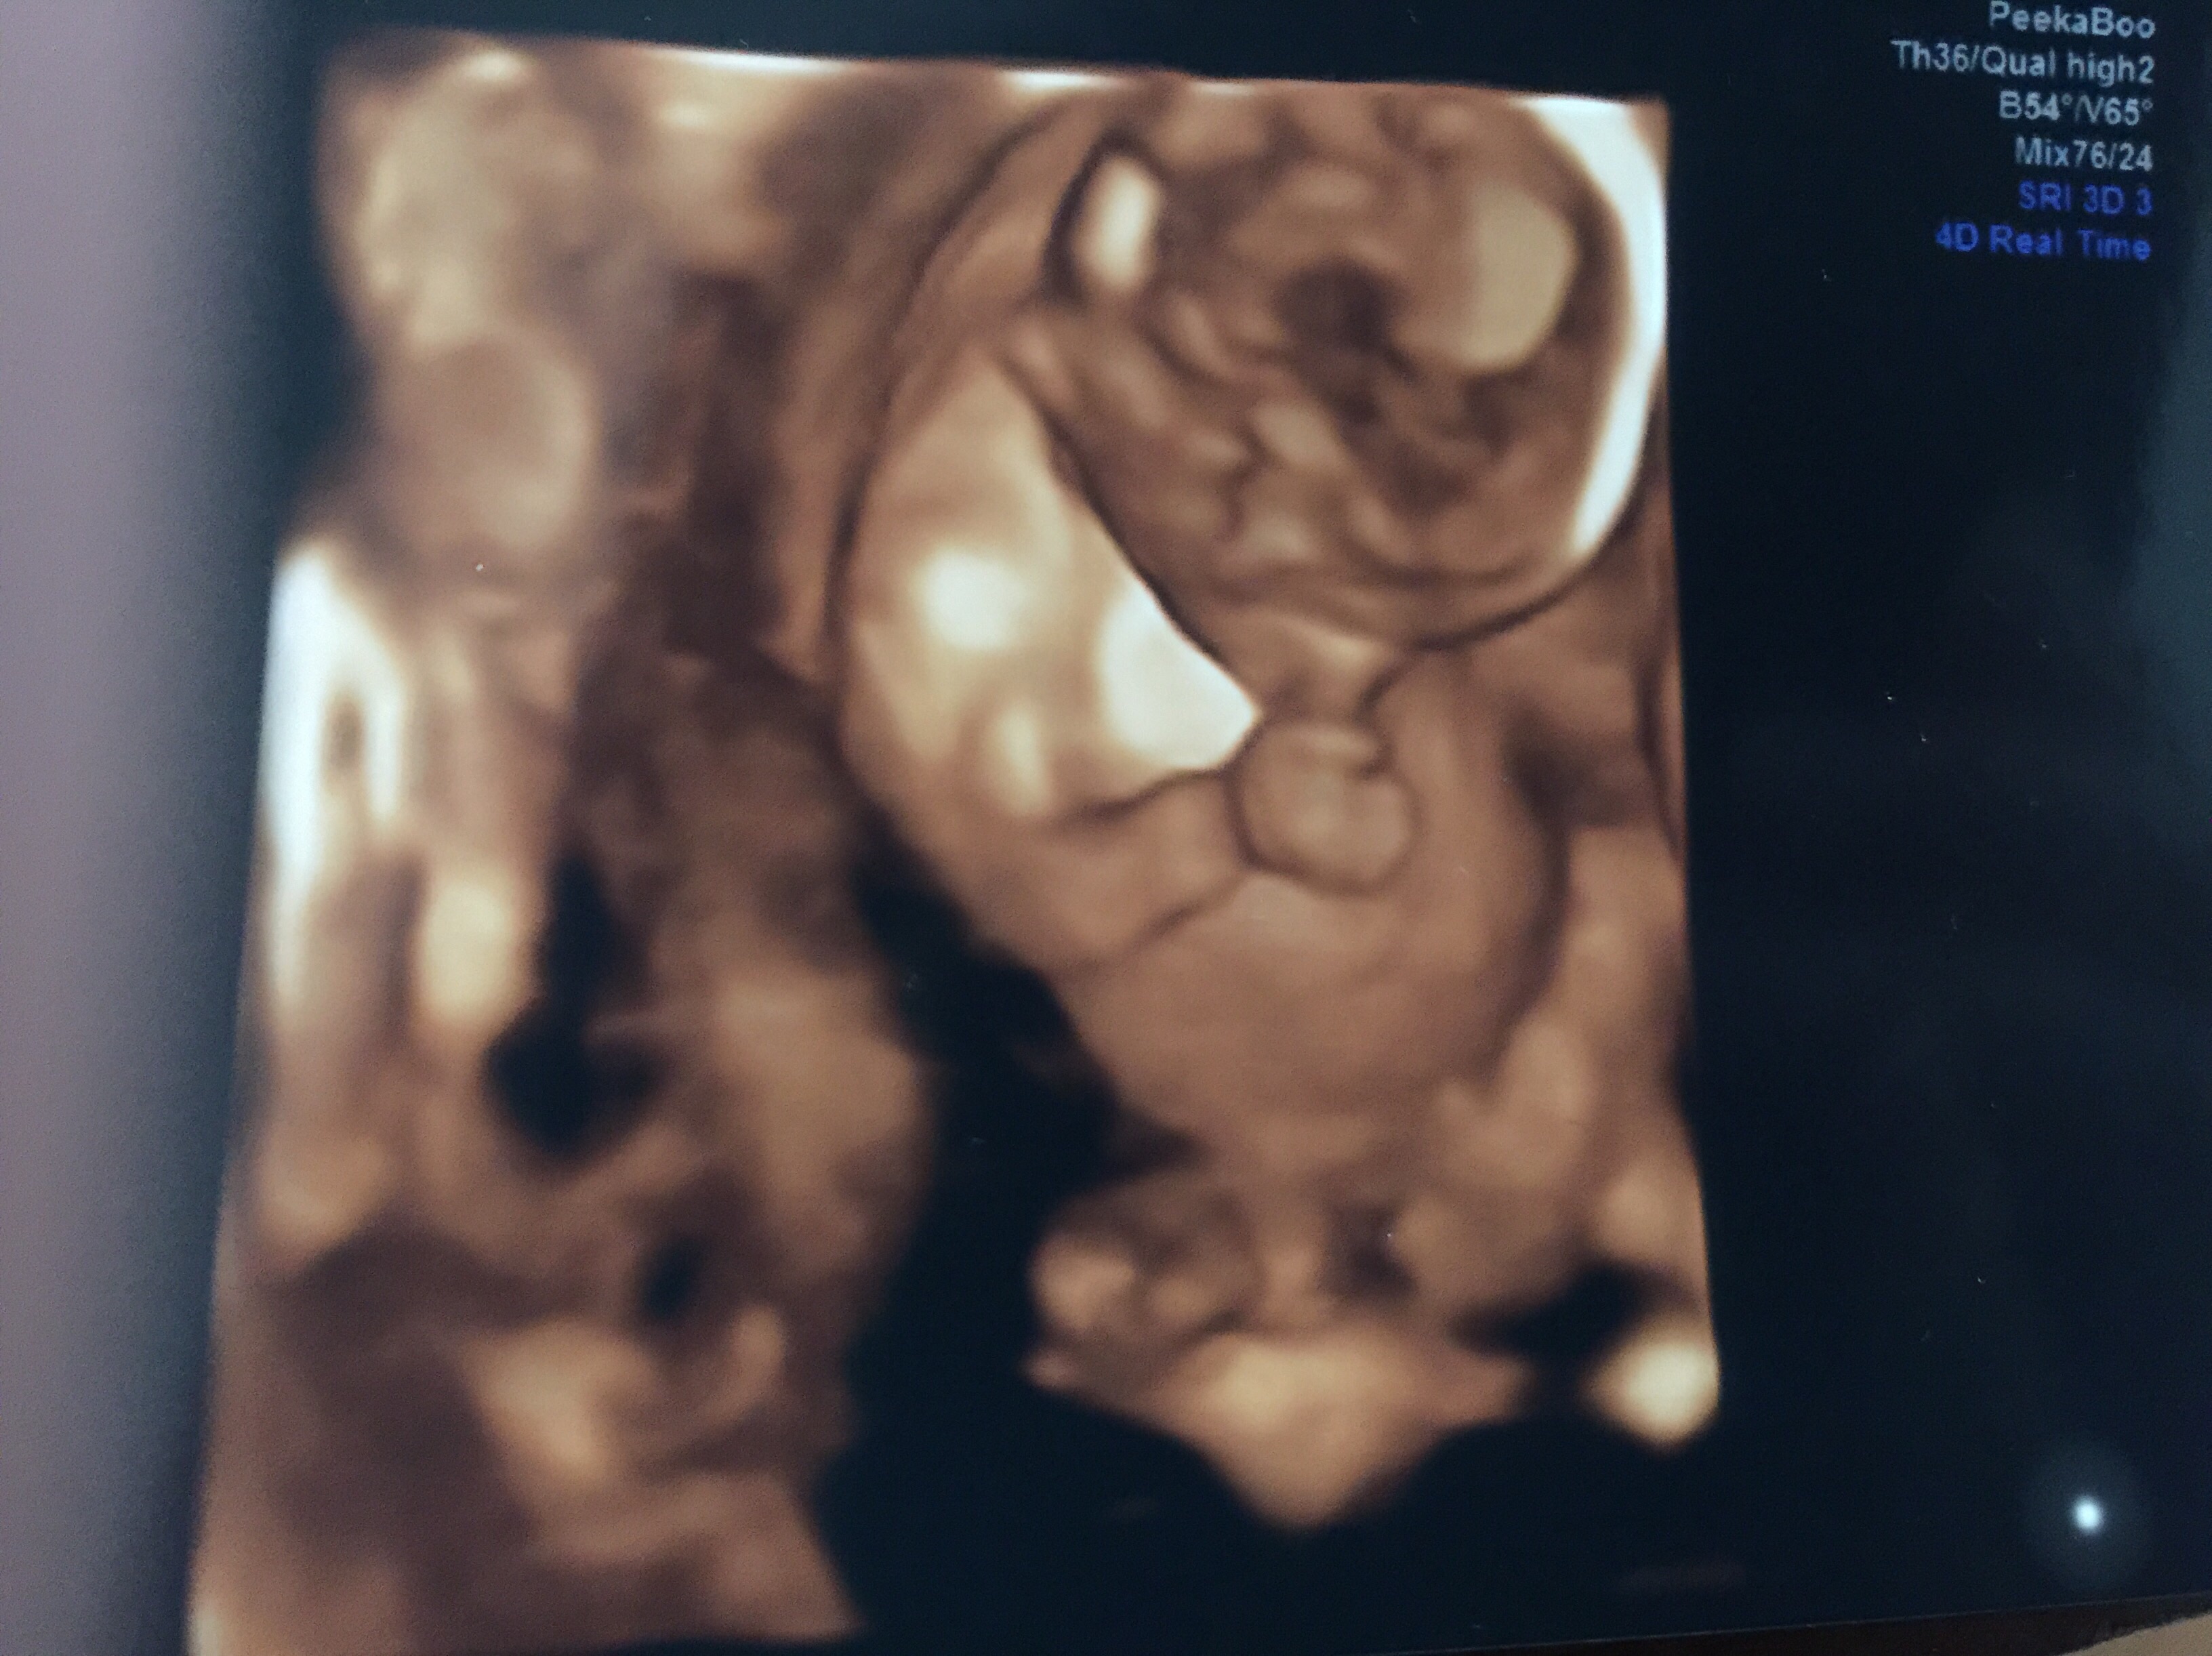

It's a Boy

He wouldn't stop sucking his thumb. It was so cute.